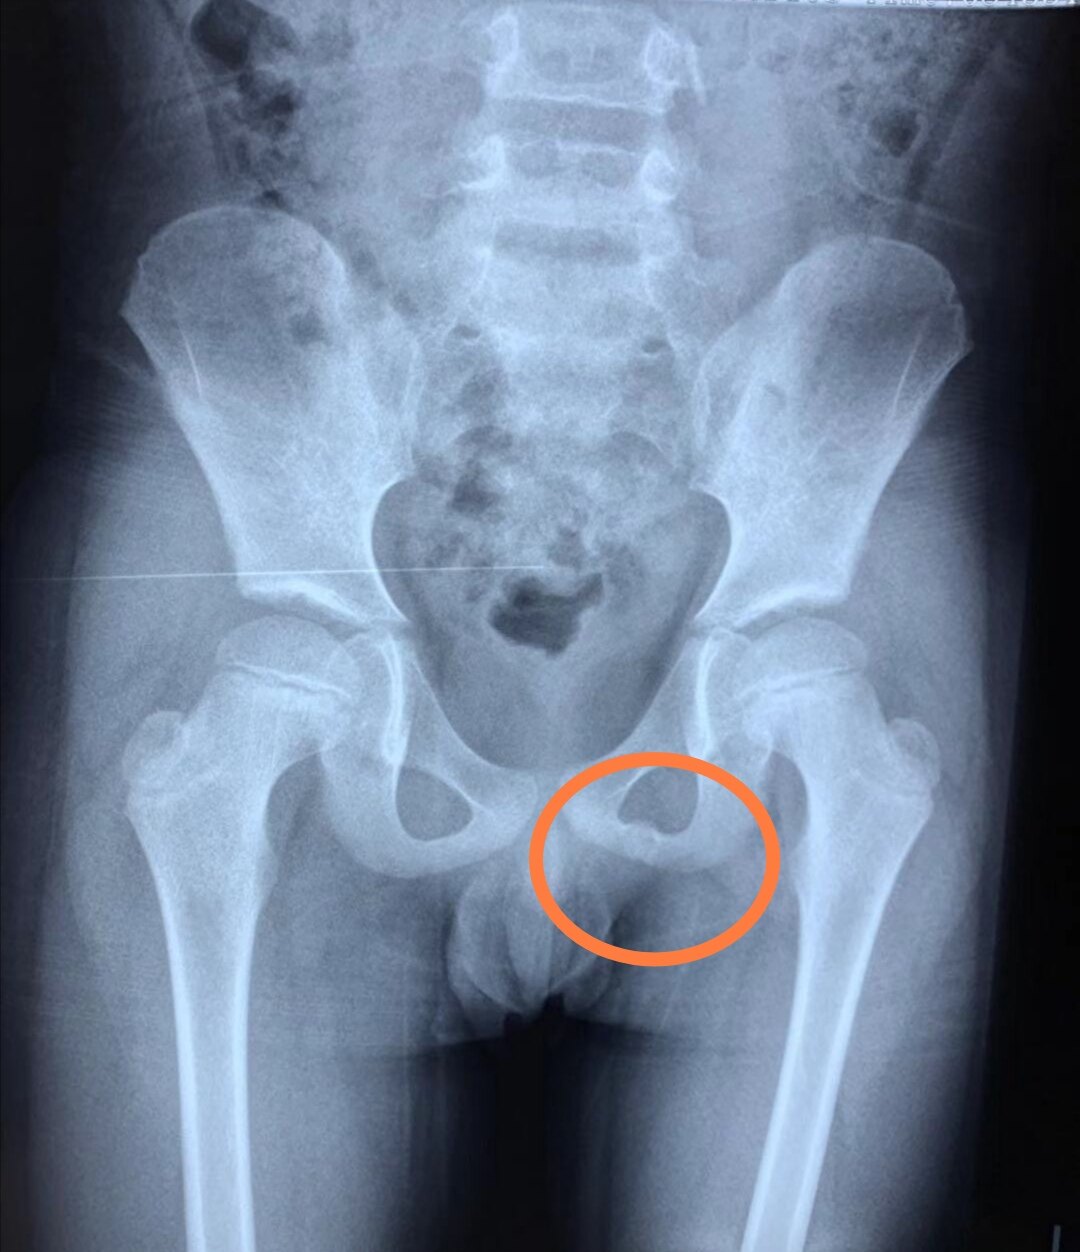

08/03/16 · 恥骨炎は、恥骨結合で炎症が起きてしまう症状で、恥骨結合炎ともいわれます。 恥骨結合は原則動かない部分なのですが、 激しい運動 や 妊娠・出産 などで動きが生じ、炎症を起こして痛みを伴います。 恥骨付近には、上恥骨靱帯や内転筋、腹直筋などたくさんの筋や腱があります。恥骨結合炎は,恥骨結合,股関節,軟骨に機 械的な炎症が生じるために,鼠径部痛を呈する 疾病である.アスリートではサッカー選手によ くみられ,骨盤X線撮影,CT(computed tomography)にて恥骨融解像, MRI(magnetic reso恥骨痛の主な原因 主な原因 妊婦さんではないのに恥骨痛が起きる場合の主な原因は、 骨盤の歪みと恥骨結合炎、恥骨骨折 によるものです。 恥骨痛は妊娠中、お腹が大きくなるにつれて痛みが出ることが一番多いです。

グロインペイン症候群(恥骨痛)の治し方 恥骨痛を解消するためには、まず、押さえると痛い恥骨痛なのか、曲げると痛い恥骨痛なのかを把握する必要があります。 そして、それぞれのタイプに応じた適切な箇所をしっかり押さえ、股関節を動かすことで痛みをとることができます。 施術をする人、される人の様子を動画で解説するので、実際の動きを理解する骨盤部骨髄炎は全骨髄炎中25%と比較的まれ で 恥骨坐骨軟骨結合(ischiopubic synchondrosis:IPS)骨髄炎はそれ以下の頻度であるが 感染を起こす部位としては重要であると報告され ている웋웦웏웗IPSは従来のシンチグラフィーやX線使により恥骨間円板に炎症を生じる疾患で,整形外科領域では一般的な炎症性疾患であ る.一方で,化膿性恥骨結合炎(septic arthritis of the pubic symphysis,以下SAPS)

Ture,悪性骨腫瘍,骨髄炎などが挙げられる。 われ われは最近,恥骨部に単純X線像で骨硬化像を呈 する診断不明な2症例に骨生検をおこなった。恥骨骨髄炎は全骨髄炎の1%以下で,稀な疾患とさ れているi) 難治性の恥骨骨髄炎では腸脱機能が荒廃 し,恥骨切除および勝脱全摘術と尿路変向術が必要に なる場合や,経過によっては致命的となることがある とされている2)今回,ロボット支援下前立腺恥骨結合炎(groin pain syndrome) 鼠径部痛症候群・グロインペイン症候群とは 以前に恥骨結合炎の記事を書いたのですが、治癒された方の続報が入りましたので掲載致しますね。元気走で良